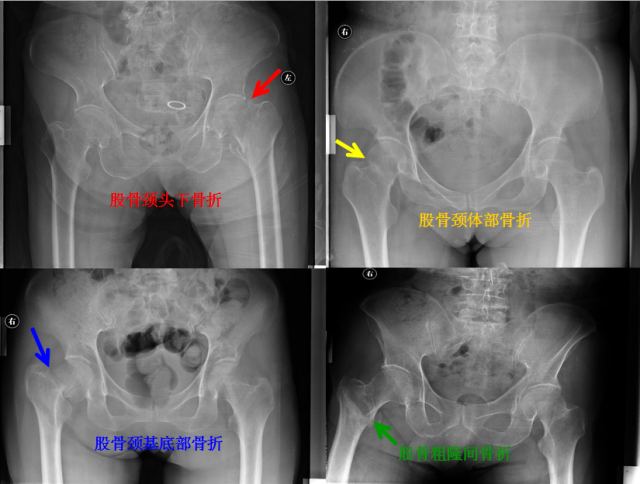

骨折篇

01

定义:骨折{Fracture}是指骨的完整性和连续性的折裂或粉碎。包括创伤性骨折、疲劳性骨折和病例理性骨折。 临床上以创伤性骨折*常见。